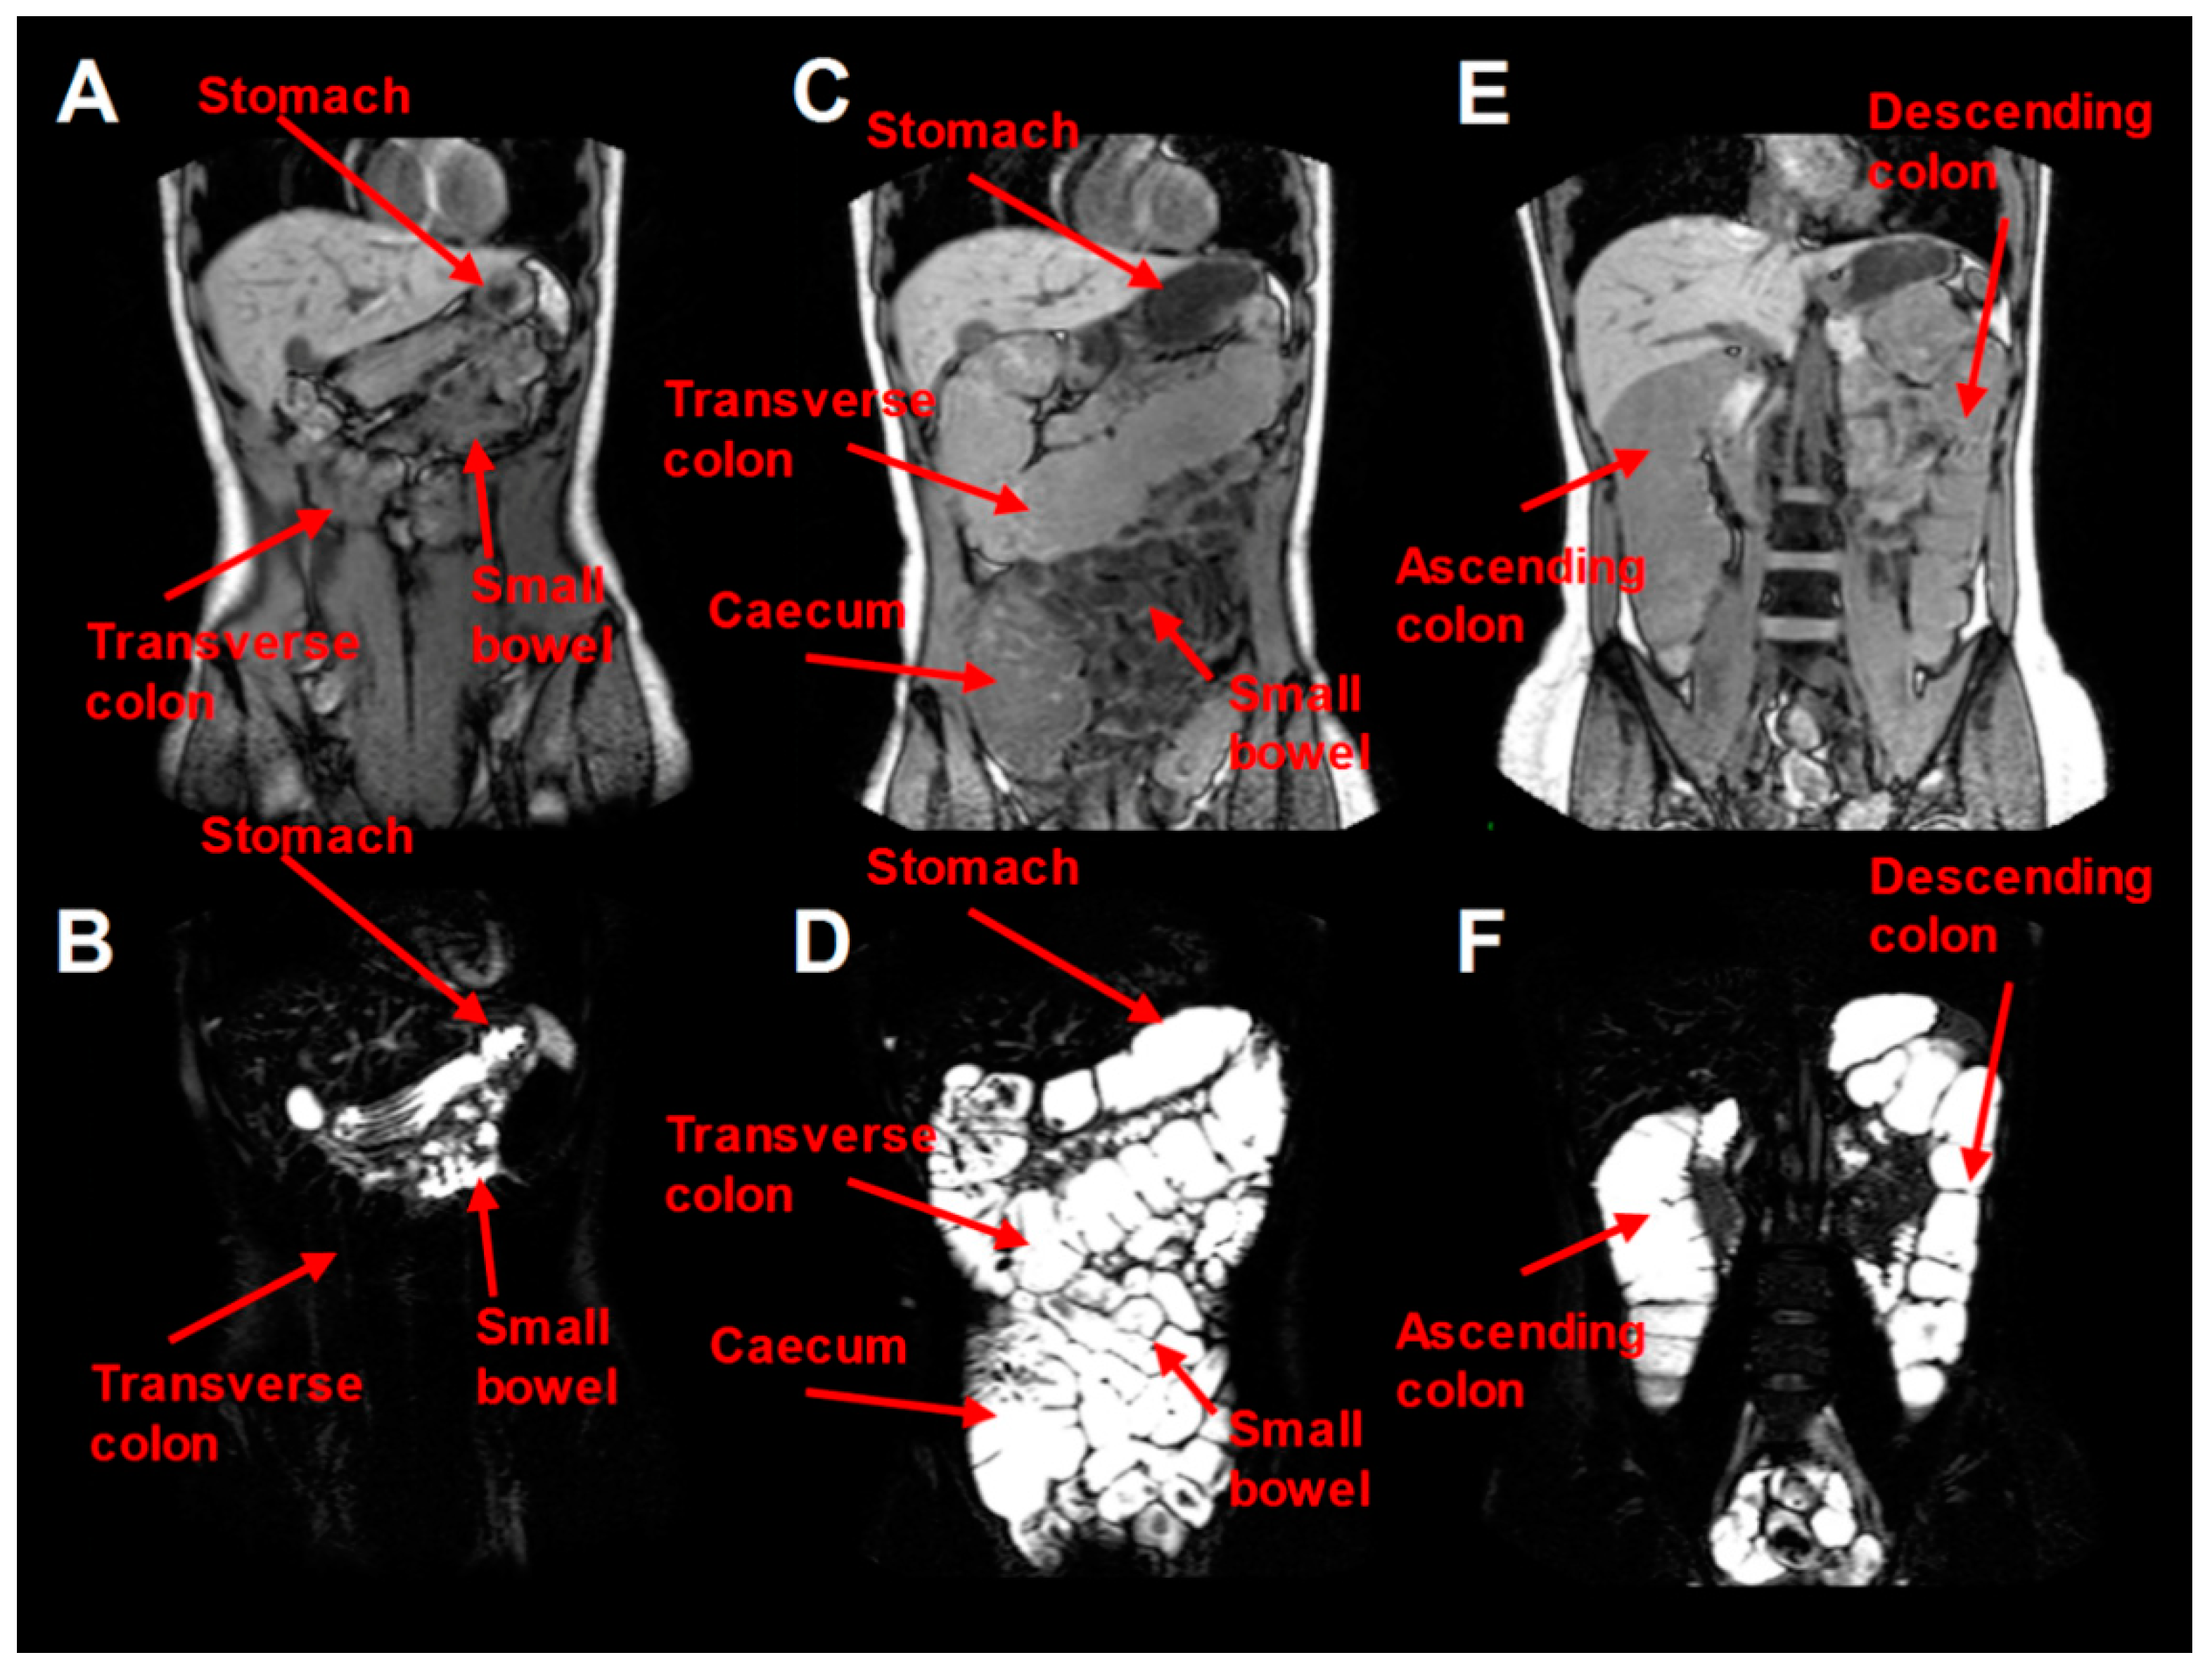

2. Colon Anatomy and Physical Dimensions